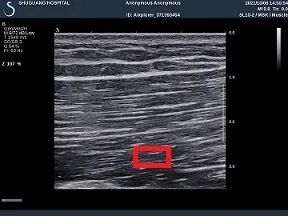

在解剖下,會看到“筋”是肌肉中

顏色更深(紅)的那一部分。

正常的筋平整柔順、富有彈性和力量,

受傷後的筋一絲一絲的纖維破損了,

排列紊亂,會攣縮在一起結成了疙瘩。